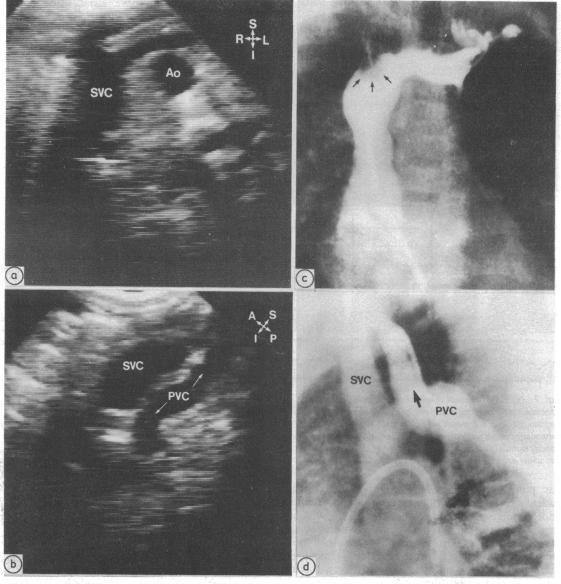

Total anomalous pulmonary venous connection can be diagnosed by cross sectional echocardiography. Information is, however, lacking concerning the diagnostic accuracy of this imaging method and any factors which may influence it. To predict the pulmonary venous connection 463 patients with congenital heart disease who had angiographic confirmation were prospectively examined. Total anomalous pulmonary venous connection was present in 34 (7%) patients and correctly detected in 33 (97% sensitivity). There were two false positive results (99% specificity). All 23 patients with atrial situs solitus with or without associated congenital heart defects were correctly detected. One false negative result occurred in a patient with right atrial isomerism and complex congenital heart disease with decreased pulmonary blood flow. Diagnosis of the type of total anomalous pulmonary venous connection, including the site and other anatomical details, was analysed and was correct in 24 of 34 (71%) patients. Errors included incorrect prediction of the site of total anomalous pulmonary venous connection in five patients with right atrial isomerism, atrioventricular canal defect, and pulmonary atresia, details of confluence interconnection in three of four patients with the mixed type of connection, undiagnosed pulmonary venous obstruction in three of the patients with right atrial isomerism, and failure to predict common pulmonary vein atresia in one patient. Factors which were related to incorrect echocardiographic diagnosis were abnormal atrial situs, mixed total anomalous pulmonary venous connection, and associated congenital cardiac defects, whereas age, weight, sex, clinical condition, and time during the study were not related. It is concluded that cross sectional echocardiography can be used to diagnose accurately total anomalous pulmonary venous connection. This method can be the definitive imaging and diagnostic method in symptomatic infants with total anomalous pulmonary venous connection who have atrial situs solitus, unifocal pulmonary venous connection, and no evidence of other major congenital cardiac defect.

完全性肺静脉异位连接可通过横断面超声心动图诊断。然而,关于这种成像方法的诊断准确性以及可能影响其的任何因素,目前尚缺乏相关信息。为预测肺静脉连接情况,对463例经血管造影证实的先天性心脏病患者进行了前瞻性检查。34例(7%)患者存在完全性肺静脉异位连接,其中33例(敏感性97%)被正确检测出。有2例假阳性结果(特异性99%)。所有23例心房正位且伴有或不伴有相关先天性心脏缺陷的患者均被正确检测出。1例假阴性结果出现在1例右心房异构且患有复杂先天性心脏病并伴有肺血流量减少的患者中。对完全性肺静脉异位连接的类型,包括部位及其他解剖细节进行了分析,34例患者中有24例(71%)诊断正确。错误包括:5例右心房异构、房室管缺损和肺动脉闭锁患者中完全性肺静脉异位连接部位预测错误;4例混合型连接患者中有3例汇合连接细节未被诊断出;3例右心房异构患者中有3例未诊断出肺静脉梗阻;1例患者未预测出共同肺静脉闭锁。与超声心动图诊断错误相关的因素为心房位置异常、混合型完全性肺静脉异位连接及相关先天性心脏缺陷,而年龄、体重、性别、临床状况及研究期间的时间与之无关。结论是,横断面超声心动图可用于准确诊断完全性肺静脉异位连接。对于有症状的完全性肺静脉异位连接婴儿,若其心房正位、肺静脉连接单一且无其他主要先天性心脏缺陷证据,该方法可作为确定性的成像和诊断方法。